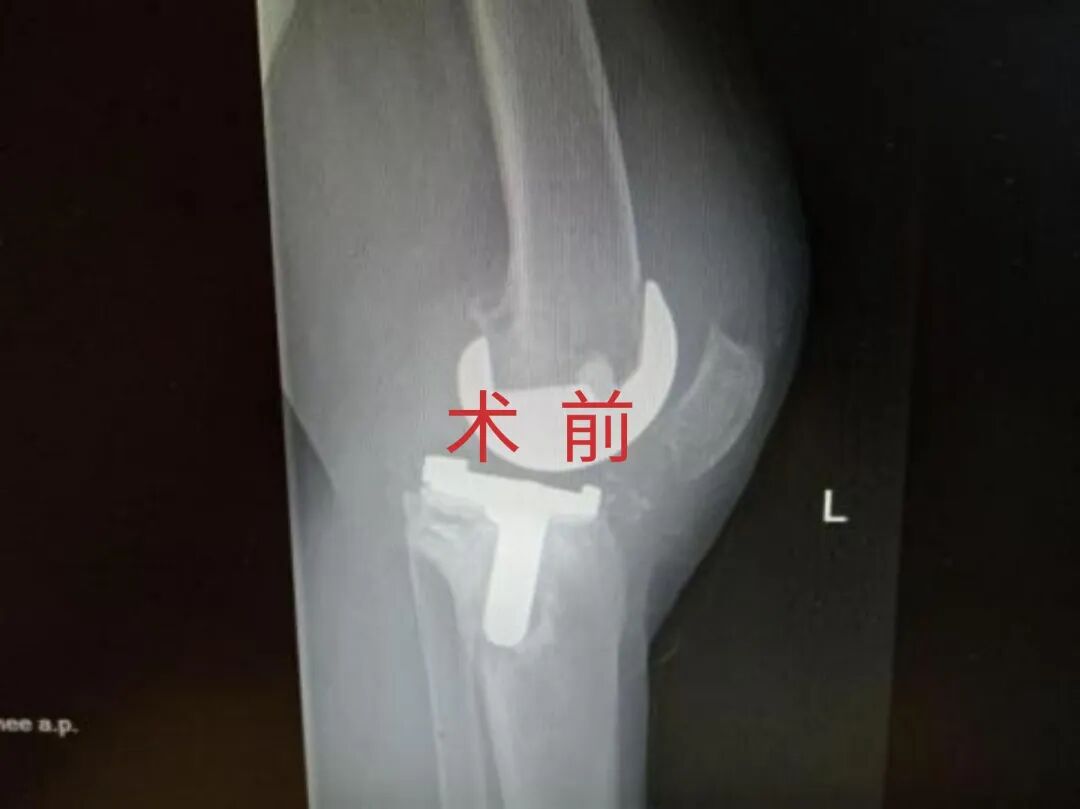

4月23日,贵州航天医院第58次晨读会由我院骨科副主任医师张艳金作学术交流,他以“加速康复指导下的快速手术”为题,详细讲解了老年股骨粗隆间骨折与儿童四肢骨折的临床诊疗难点,结合加速康复外科(ERAS)核心理念,重点阐述了ERAS理念在两大人群中的创新实践,实现患者入院后6至24小时内即可接受手术治疗。针对老年髋部骨折患者,提出通过多学科协作(MDT)与微创手术优化围术期管理,在确保安全前提下缩短术前等待时间,实施精准化麻醉及术后康复方案,可有效降低并发症发生率、改善患者生活质量和预后效果。在儿童骨折领域,强调微创术式与心理干预并行的双轨策略,既减少手术创伤对骨骼发育的影响,同时关注患儿心理疏导,实现生理功能与心理健康同步康复。并通过典型案例的影像学资料与随访数据,直观展示了ERAS理念指导下骨科治疗模式的创新成果。 贵州航天医院骨科 专家简介 赵学平 中共党员,骨科党支部书记、主任,主任医师 临床擅长:从事骨科临床工作30余年,对骨科常见疾病的诊治具有丰富的临床经验。 世界中医药联合会脊柱康复专业委员会常务理事,中华中医药学会整脊分会常务委员,中国中西医结合学会骨伤科分会肢体矫形功能重建与康复专家委员会常务委员,中国研究性医院学会骨科创新与转换专业委员会关节外科学组保髋工作委员会常委,中国康复技术转化及发展促进会骨外科与康复技术转化专业委员会常务委员,泛珠三角区域运动医学联盟(PPRD-SMA)理事会常务理事,中国研究型医院学会运动医学专业委员会委员,贵州省中医药学会整脊分会副主任委员,贵州省中西医结合学会银质针专业委员会副主任委员,贵州省康复医学会骨与关节专业委员会常务委员,贵州省人民医院骨科专科联盟常务理事,贵州省康复医学会骨内科专业委员会常务委员,中华医学会贵州省骨科学会委员,贵州省康复医学会脊柱脊髓专业委员会常务委员,贵州省运动医学分会委员,贵州省康复医学会骨与软组织肿瘤专业委员会委员,遵义市医学会创伤分会副主任委员,贵州省康复医学会骨内科专业委员会遵义地区分会常务委员,遵义市医疗事故鉴定、伤残鉴定、工伤鉴定、司法鉴定专家。 长期从事骨科临床研究及教学工作,在国家级、省部级杂志发表论文20余篇,SCI论文2篇,参与主编骨科专著2部,主持省部级科研项目2项,参与指导省部级、市级科研项目6项。 陈明勇 骨科副主任,副主任医师 临床擅长:从事创伤骨科工作约20年,对骨缺损、骨不连、骨肿瘤、肢体畸形等的肢体矫形重建及功能重建,慢性化脓性骨髓炎的根治治疗、糖尿病足的保肢治疗、快速康复理念(ERAS)下的老年骨折的诊治,四肢复杂骨折的诊治,四肢骨折等微创手术治疗具有丰富的临床经验。 2004年毕业于遵义医学院临床专业,曾在中国人民解放军总医院、广西医科大学第一附属医院、上海第六人民医院骨科进修。中国中西医结合学会骨伤科专业委员会横向骨搬移治疗糖尿病足及微血管网再生学组首届委员,遵义市医学会创伤分会常务委员。 瞿 辉 中共党员,骨科副主任医师 临床擅长:对骨科的常见病、关节外科、脊柱外科及运动医学疾病的诊治具有丰富的临床经验,熟练掌握骨科手术操作技术。 毕业于遵义医学院临床医学系,2005年前往广州中山大学第一附院骨显微医学部进修学习,2011年前往成都华西医院进修学习,并多次在省内外学习骨科相关知识,是中华医学会骨科分会会员。 赵兴东 骨科主任医师 临床擅长:擅长骨科的常见病及各种创伤、四肢骨折创伤修复、骨感染、手足疾病的诊治和手足体表畸形的矫形整复,熟练掌握骨科四肢骨病及创伤的手术操作技术,尤其在四肢关节复杂性损伤、手足外伤、组织缺损创面、难治创面的皮瓣修复方面及平足、高弓足矫形方面及四肢慢性疼痛诊治、康复方面具有丰富的临床经验。 硕士研究生,毕业于遵义医学院临床外科系,2015年前往山东省立医院手足外科进修学习;遵义市医学分会创伤分会第一、二届委员,遵义市手外科医学会第二委届员会常务委员;在省级及省级以上期刊发表文章9篇,参编著作2部,参与主持并完成市级课题1项,参与市级课题2项、省级课题1项。 张艳金 中共党员,骨科副主任医师 临床擅长:从事骨外科工作16年,对复合伤、多发伤的救治、四肢骨干骨折、关节周围骨折、骨肿瘤、骨髓炎等诊治具有丰富的临床经验。 中共党员,硕士研究生,2006年本科毕业于山西医科大学第二临床医学院,2011年研究生毕业于北京军区总医院;在“老年COPD患者合并髋部骨折的诊治”国际合作课题组研究两年,在老年髋部骨折的诊治方面具有丰富的经验,并发表论文6篇;主持遵义市级课题1项,承担遵义医科大学的临床教学工作,获得遵义医科大学优秀带教老师荣誉。编撰有《骨科疾病诊疗精粹》一书,开展2项新技术,编撰地方规范《务川自治县创伤骨科常见疾病诊疗规范》一书。 张俊凯 骨科副主任医师 临床擅长:从事骨科临床工作28年,对创伤骨折、骨感染、骨缺损、骨不连等外科诊治,四肢骨折的微创手术治疗,四肢复杂骨折(如关节内粉碎性骨折、多发骨折等)的损伤控制及手术治疗等具有丰富的临床经验。 1995年毕业于遵义医学院临床专业,2009年前往复旦大学附属医院骨科进修1年。 卢懿明 中共党员,骨科副主任医师 临床擅长:从事骨科工作18年,对创伤骨折、四肢骨折的微创手术治疗、四肢复杂骨折(如关节内粉碎性骨折、多发骨折等)的损伤控制及手术治疗,尤其是髋部骨折的PFNA等微创技术,踝关节骨折、膝关节周围骨折的Mipo微创技术等具有丰富的临床经验,开展了4项新技术,发明6项新型专利技术。 2005年毕业于遵义医学院临床专业,2017年,前往南方医科大学第三附属医院骨科进修半年,回院后运用Mipo技术对骨干骨折及干骺端骨折的治疗技术,同时积极开展骨盆骨折、髋臼骨折腹直肌外侧切口的应用;发表了多篇专业论文,经常参与省内外学术交流会授课,获得医院荣誉称号多个。 邬夏荣 骨科副主任医师 临床擅长:从事骨科工作16年,对四肢复杂骨折、骨肿瘤的诊治,尤其是足踝创伤、慢性踝关节损伤、平足症等诊疗具有丰富的临床经验。 2006年毕业于遵义医科大学临床医学专业,曾在陆军军医大学西南医院进修学习,发表多篇骨科学术论文。 余德怀 中共党员,骨科副主任医师 临床擅长:从事骨科工作10余年,对运动医学、骨关节、脊柱外科常见病、多发病的诊治具有丰富的临床经验。 硕士研究生,2011年毕业于遵义医学院临床医学专业,曾前往遵义医科大学附属医院运动医学专业进修学习;是贵州省医学会运动医学分会青年委员,西部关节镜联盟委员;发表多篇骨科学术论文。 冯 乾 骨科副主任医师 临床擅长:从事骨科工作近20年,熟练掌握骨科多发病及常见病的诊治,尤其对脊柱退变性疾病的诊断及治疗具有丰富的临床经验,主要研究脊柱微创相关治疗方式,能熟练开展椎间孔镜及UBE。 曾前往北京大学第三医院进修学习疼痛及椎间孔镜、首都医科大学友谊医院专业进修脊柱内镜;是贵州省康复医学会第三届脊柱脊髓专业委员会委员;发明专利3项、发表脊柱外科专业论文多篇。 赵小锋 中共党员,骨科副主任医师 临床擅长:从事骨科临床工作11年,对骨科常见病、多发病诊疗有较为丰富的临床经验,擅长脊柱相关疾病诊断及治疗,尤其是颈、腰、腿疼痛疾病诊断及治疗,擅长胸腰椎骨折微创经皮穿刺内固定术、经皮穿刺椎体成形术、经皮穿刺脊柱内镜下腰椎间盘摘除术、单纯开创腰椎间盘摘除术、腰椎滑脱复位椎间植骨椎融合内固定术、腰椎管狭窄减压融合内固定术及人工髋、膝关节置换术等。 2012年毕业于遵义医学院外科学专业硕士研究生,2019年参加“遵义市115医学人才精英计划”于上海交通大学第一附属医院培训学习,2023年于北京大学第三人民医院脊柱外科进修学习,曾获得遵义市优秀医师荣誉称号。 遵义市手外科第一届委员,遵义市医学会创伤分会第一届委员,遵义市医学会创伤分会第二届委员,贵州省康复医学会第三届脊柱脊髓专业会委员,遵义市医学会烧伤与整形外科学分会委员,发表论文5篇,其中国家级核心期刊1篇,SCI论文1篇,主持市级课题1项并结题,参与市级课题2项。 贵州航天医院骨科 简介 基本情况 贵州航天医院骨科组建于20世纪60年代,前身是以创伤和断肢(断指)再植闻名于世的上海市第六人民医院骨科,中国断肢(断指)再植的奠基者、中科院院士陈仲伟等著名专家、学者多次莅临科室指导医疗、教学,是贵州省最早拥有专业骨科技术科室之一,在70年代开展了贵州省首例断肢(断指)再植手术。组建50余年来,诊治患者已逾百万,挽救了无数的伤病员,成为了保障遵义地区人民群众健康的重要支撑。 经过几代人的不懈努力,今天的骨科,已由创伤骨科发展至骨病、骨肿瘤、骨结核等领域,现有脊柱外科、关节外科、四肢创伤、手足外科四个亚专科,成为了集医疗、教学、科研于一体的综合学科,是贵州省临床重点专科、遵义市临床重点专科、遵义市骨科临床医学中心、遵义市基层骨科专科联盟理事长单位。 科室目前开放床位110张,共有医护人员50余人,副高级以上专家18人,硕士研究生15人。拥有一流骨科医疗设备多台,每年不定期选派优秀技术骨干到全国各大知名医学院校进修、学习、参观、交流,并邀请国内、国外知名专家教授来院进行交流、指导,通过不断引进国内外先进的诊疗技术,科室医疗技术水平稳步提升,为广大人民群众提供了优质的医疗服务。 专科特色 骨一科 (一)骨缺损、骨不连的肢体与功能重建 胫骨横向骨搬移技术治疗糖尿病足: (二)慢性骨髓炎的根治治疗 (三)肢体缺血性疾病如糖尿病足、脉管炎的保肢治疗 (四)皮瓣修复 (五)复杂创伤的治疗 (六)老年髋部骨折及小儿骨折快速手术 老年髋部骨折: 骨二科 (一)胸腰椎骨折微创经皮椎弓根螺钉固定术 (二)老年性骨质疏松性患者腰椎滑脱脊柱内固定术(骨水泥螺钉) (三)V形双通道脊柱内镜技术(VBE)腰椎融合术治疗腰椎退行性疾病 (四)老年性骨质疏松性骨折(PVP/PKP)术 (五)人工髋关节置换术 (六)双侧股骨头坏死人工全髋关节置换 (七)右侧全髋置换术后假体周围骨折翻修 (八)人工膝关节置换术 (九)人工膝关节假体松动翻修 (十)关节镜技术 传统手术切口 关节镜技术切口 诊疗范围 骨一科 1.四肢创伤、矫形。 2.手、足踝外科。 骨二科 end